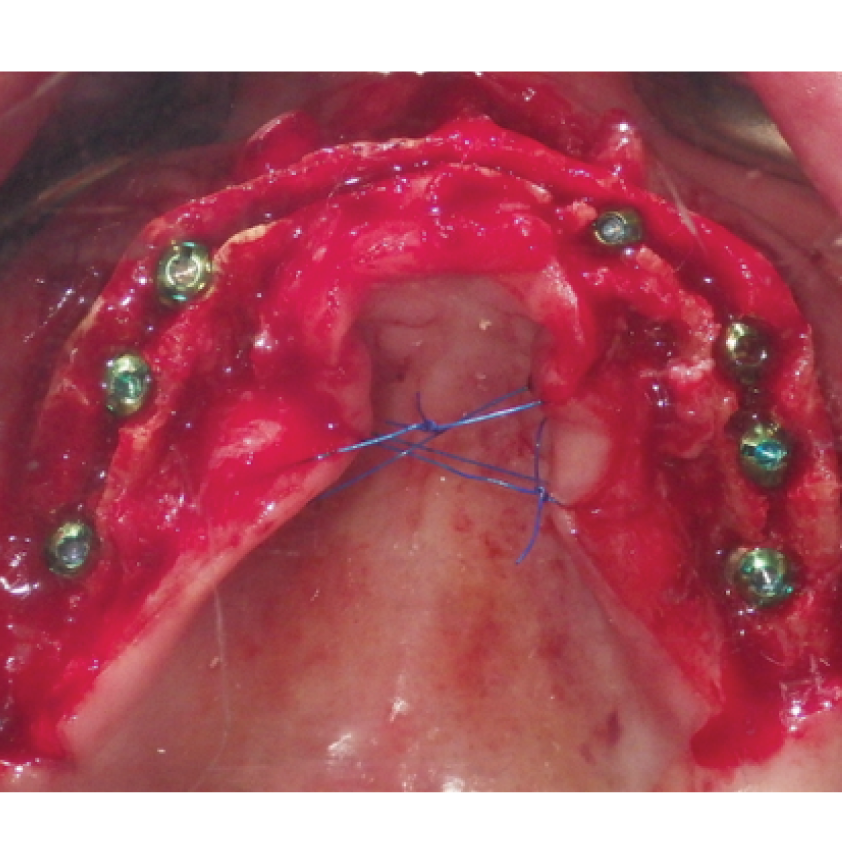

Director’s Clinical Cases

Director’s Clinical Cases